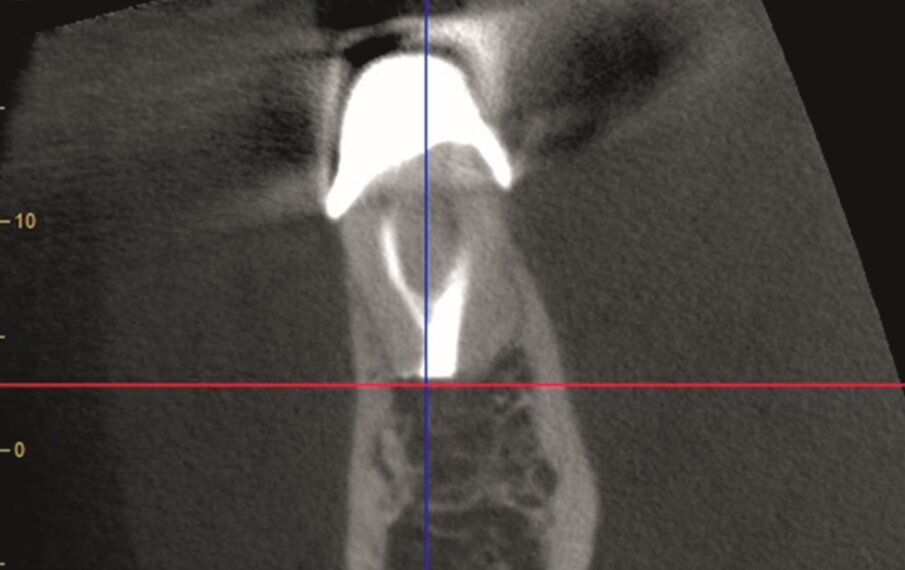

Fig. 1a–d: Pre-op CBCT scan of tooth #36. The axial (a), …

…and sagittal views (c) showed a hypo-dense zone around the apical third of the mesial and distal roots and intact cortical buccal bone.

A template that marked the limits of a cortical window to accurately reach the apical area of both roots was designed (d).

A 63 year old female patient, with a non-contributory medical history, consulted owing to moderate pain associated with her previously treated mandibular left first molar. CBCT revealed that a mesiobuccal canal had being missed during initial treatment, that the mesial and distal roots were affected by an apical lesion, and that the cortical buccal bone was intact.

Retreatment was done in two appointments, and calcium hydroxide was used as the intra-canal dressing after removing the previous filling material and cleaning and shaping three canals. After one week, root canal therapy was completed. Two months later, symptoms persisted and clinical examination revealed pain on vertical percussion; periodontal probing depth and mobility were within normal limits. CBCT revealed no signs of bone healing (Figs. 1a–c). The diagnosis for tooth #36 was previously treated symptomatic periapical periodontitis, and the treatment of choice was guided EMS.

An intra-oral scan (TRIOS, 3Shape) of the mandible, and the resulting STL file was combined with the DICOM files of the CBCT scan to plan a surgical guide using the Blue Sky Bio software. A template that marked the limits of a cortical window to accurately reach the apical area was designed and printed (Fig. 1d).